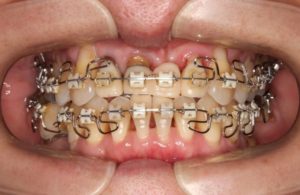

上記の写真は2年間派の矯正治療を行なったところです。治療前と比べ、上下顎の歯並びの位置のバランスが取れて、隙間なくキレイに上下の歯と歯がかみ合っていることが分かります。

上顎の前歯は治療前より被せ物だったので、矯正治療後の歯並びに合わせて、まずは保定期間中に仮の歯を修正しています。歯の矯正治療が終了すると、キレイな歯並びに移動した歯を固定する為の保定期間に移ります。保定期間は症例の状況によって異なりますが、一定期間リテーナーという歯並びを固定する為の取り外し式の装置を、歯磨きと食事の時以外24時間はめます。これは骨折した場合、骨が固まるまでギブスをするのと同じような役割です。